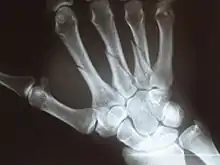

Wrist and hand injury

Wrist mobility is often restricted due to inflammation of the forearm muscles as they contract and tighten due to injury.[2] Most wrist dislocations occur between the capitate and the lunate.[16][17] Carpal fractures are caused by falling on an outstretched hand the wrist is hyper-extended in ulnar deviation with a component of rotation.[17] Swelling of the Median nerve tissue leads to nerve entrapment ultimately resulting in restriction of movement, other symptoms include; pain, numbness and weakness.[1] DeQuervain’s Tenosynovitis is a form of tendinitis of the muscles that move the thumb.[2]